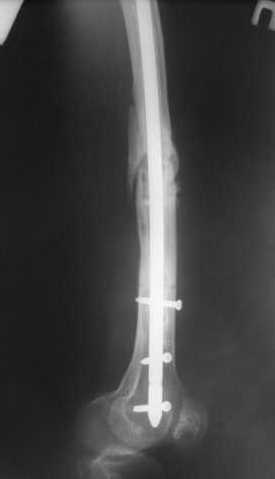

Спицы оставлять не надо. Надо их убрать, но перед этим ввести винт-poller. Такая необходимость возникает в редких случаях, когда можно ожидать смещения длинного отломка. Спицы из короткого отломка после введения запирающих винтов можно удалять без риска смещения.

В приложении пример, дистальный отломок пружинил кзади. Два винта потому, что первый оказался чуть кпереди и не упирался в гвоздь.